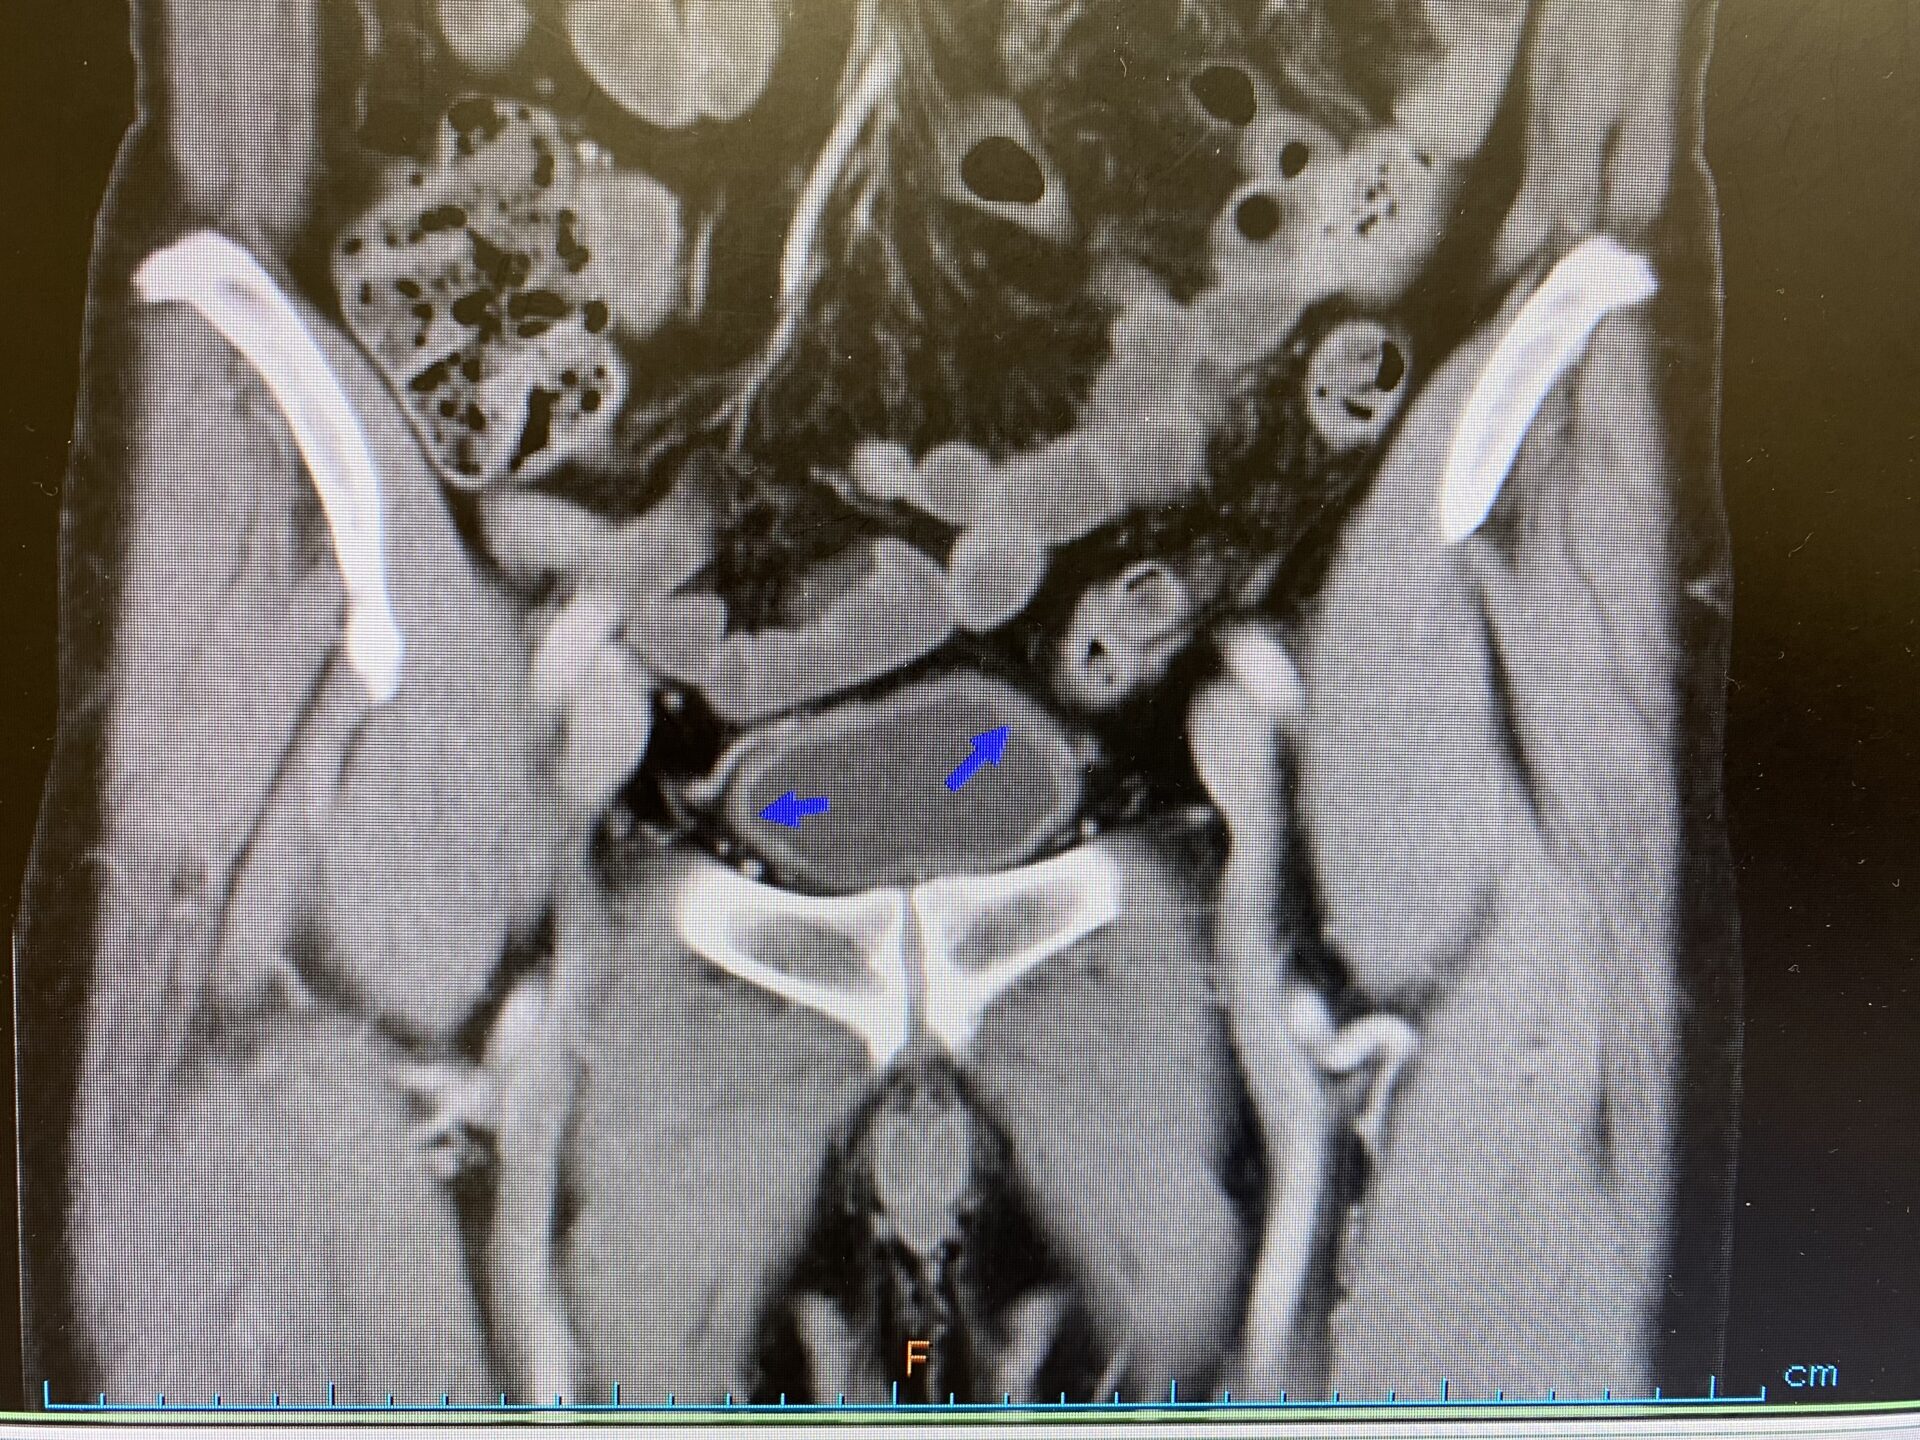

- 膀胱鏡検査: これは、カメラが取り付けられたチューブを膀胱に挿入して内壁を評価する診断検査です。医療提供者は膀胱鏡検査で膀胱容量を評価することもあります。

- 生検:膀胱鏡検査では、IC と同様の痛みを引き起こす可能性のある 癌やその他の膀胱疾患について個人を検査するために生検が行われる場合と行われない場合があります。

この結果は、膀胱痛の原因について漠然とした洞察を提供するかもしれませんが、IC を最終的に診断する唯一の方法は、フーナー病変を特定することです。ただし、これらの病変が存在しない場合でも、IC が存在しないことを意味するわけではありません。